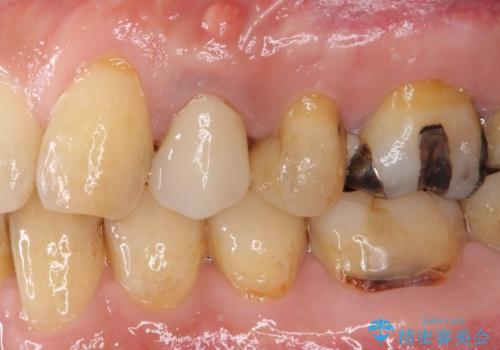

ジルコニアカスタムアバットメントは、歯肉ラインに金属が見えにくいというだけでなく、クラウンを装着する土台の形が天然歯と近い形態となるため、清掃性が高く歯肉が腫れにくいというメリットがあります。

インプラントは、人工骨を用いた際の骨誘導能が比較的高いとさせるストローマン社のSLActiveを使用しました。